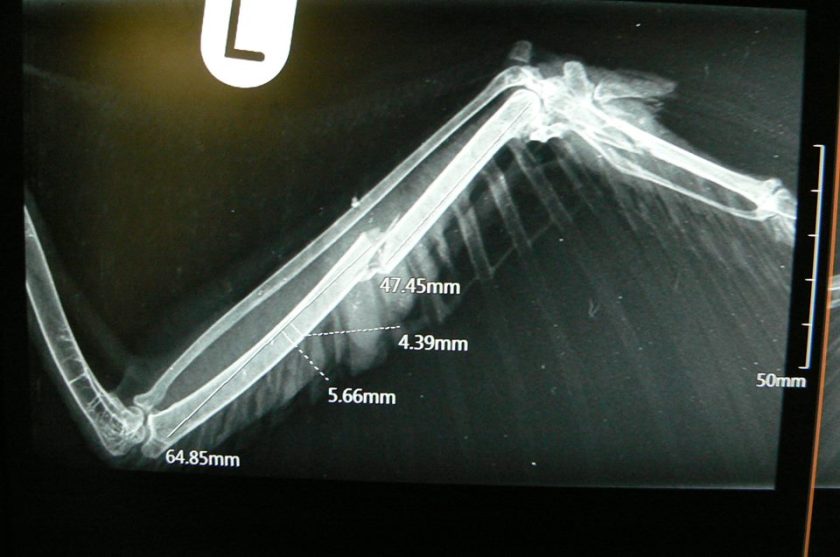

A buzzard with shot gun injuries has been found on farmland at North Frodingham, Driffield, in East Yorkshire.

It has undergone surgery to have its wing pinned and is now being cared for by Jean Thorpe of Ryedale Wildlife Rehabilitation. If you’d like to help support Jean’s never-ending voluntary efforts, please consider a donation here.